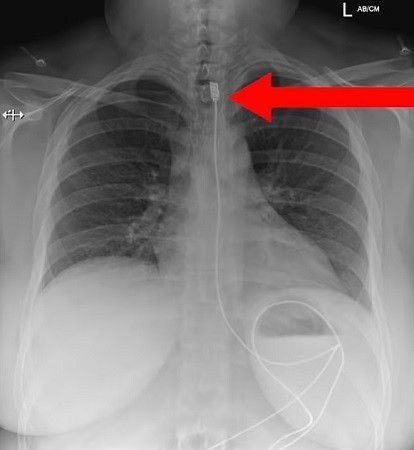

Hasil X-Ray Wanita Yang Makan Kabel (Daily Mail)